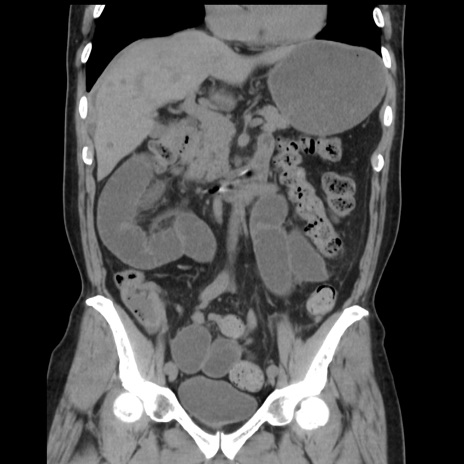

症例16(冠状断像)

【症例】 70歳代男性

【主訴】 腹痛、嘔吐

【現病歴】 約1ヶ月前より間欠的に腹痛と嘔吐あり、当院消化器内科を受診したところCTで多発する肝臓のLDAを指摘され、精査中であった。以降は消化器症状は安定していたが、2日前より嘔気と腹痛があり、同日より排便・排ガスが消失した。改善認めず、 本日、救急外来を受診した。

【身体所見】意識清明・会話良好、BT 36.3℃、BP 127/80mmHg、 P 80bpm、腹部:膨満あり、平坦・軟、上腹部正中および下腹部正中に圧痛あり、反跳痛なし、筋性防御なし。

【データ】WBC 7200、CRP 0.77